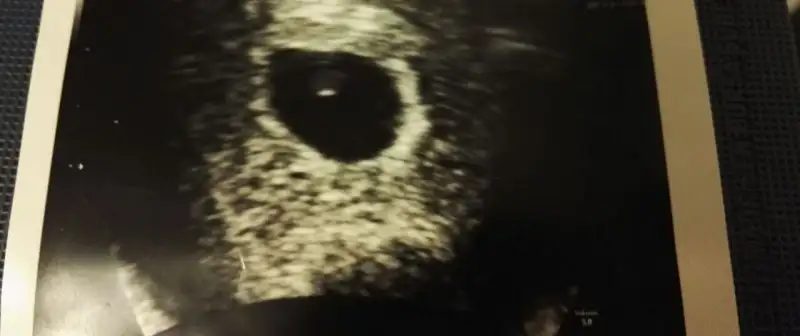

çok tatlıymış bu ya,, masallah diyorum ona.yılmadan yazıcam kızlar yatmayla falan değil kendinizi hiç sıkmayın. rahat olun. transferin 3. günü evimi süpürdüm ben, mutfağımı topladım, yemek yaptım, çamaşır bile astım. sadece dikkat ede ede yaptım. ağır ağır ama hepsini yaptım. 5. gün işe başladım. ki ortaokulda çalışıyorum yoğun bi tempomuz var. çok şükür pozitif sonucu gördüm. yatarak psikolojinizi bozacaksanız asla tavsiye etmem. ama daha iyi oluyorum diyen varsa hiç kalkmasın. ben açıkcası daraldım yattıkça 2 gün bile yeti bana fazlası çok geldi bilginizebu arada susam tanemden sevgiler teyzoşlarına Eki Görüntüle 1931971